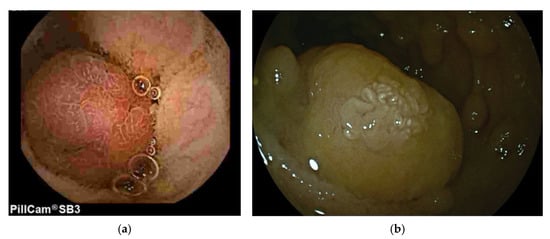

- De Palma, G.D.; Rega, M.; Ciamarra, P.; Di Girolamo, E.; Patrone, F.; Mastantuono, L.; Simeoli, I. Small-Bowel Polyps in Peutz-Jeghers Syndrome: Diagnosis by Wireless Capsule Endoscopy. Endoscopy 2004, 36, 1039. [Google Scholar] [CrossRef] [PubMed][Green Version]

- Parsi, M.A.; Burke, C.A. Utility of Capsule Endoscopy in Peutz-Jeghers Syndrome. Gastrointest. Endosc. Clin. N. Am. 2004, 14, 159–167. [Google Scholar] [CrossRef] [PubMed]